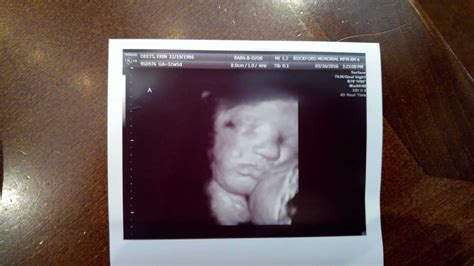

32 Weeks Pregnant Sonogram

Pregnancy is a journey filled with excitement, anticipation, and a multitude of milestones. One of the most significant milestones is the 32 weeks pregnant sonogram. This ultrasound scan provides crucial insights into the baby's development and the mother's health. Understanding what to expect during this scan can help alleviate any anxieties and prepare you for the upcoming weeks.

The 32 weeks pregnant sonogram is typically performed between 32 and 34 weeks of gestation. This scan is often referred to as the growth scan or the late anatomy scan. It serves multiple purposes, including assessing the baby's growth, checking the position of the placenta, and evaluating the amniotic fluid levels.